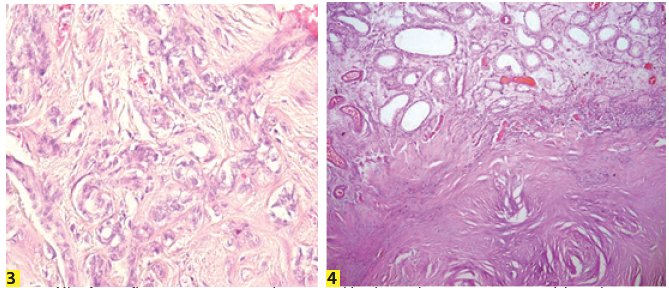

Se decide su programación para realizar orquiectomía radical izquierda, la cual se realiza sin complicaciones, con hallazgos de cordón espermático libre de neoplasia, piel de escroto libre de neoplasia, teniendo como reporte histopatológico: tumor de células de sertoli testicular, con bordes quirúrgicos libres de neoplasia, cordón libre de neoplasia, epidídimo libre de neoplasia, con bordes quirúrgicos negativos, con descripción microscópica en la que se observa: neoplasia intratesticular circunscrita compuesta por células cuboidales con atipia leve y citoplasma pálido que conforman estructuras tubulares y cordones sobre un estroma extensamente colagenizado que compone más de la mitad de la neoplasia. (Figura 1-2, 3-4). Cursando con evolución satisfactoria, con cicatrización completa de la herida, y actualmente en vigilancia, sin necesidad de tratamiento adyuvante.